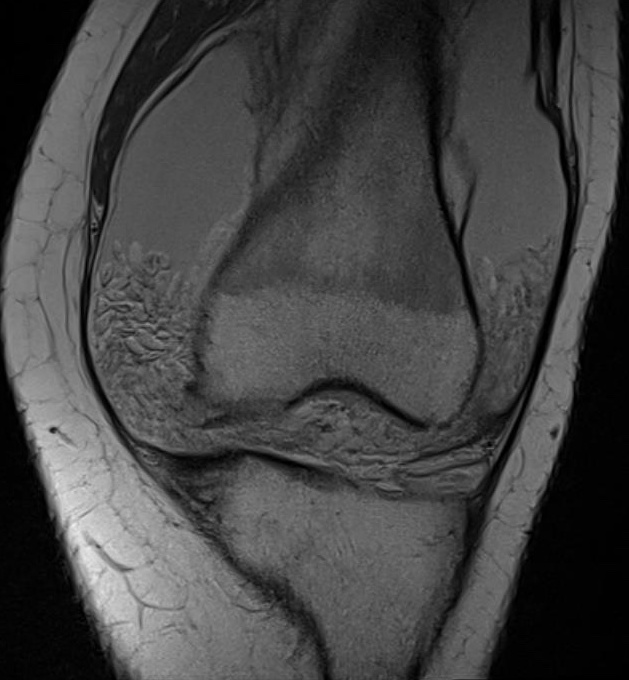

MRI

Synovial proliferation with signal similar to surrounding fat